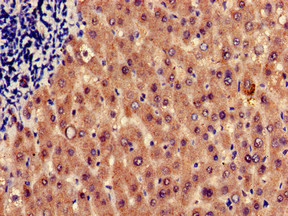

Immunohistochemistry of paraffin-embedded human liver tissue using CSB-PA010737LA01HU at dilution of 1:100